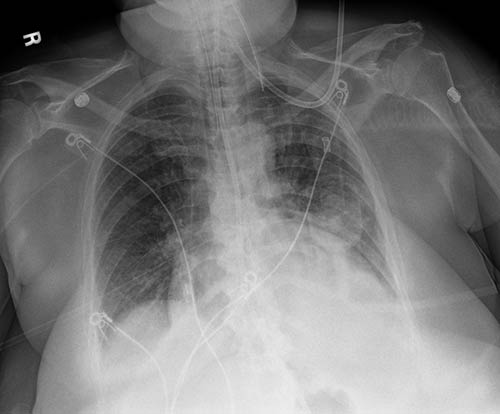

Originale

Sicurezza con una singola esposizione. Il miglioramento Tube & Line crea un’immagine complementare e utilizza un’elaborazione ottimizzata per una visualizzazione più nitida e semplice delle linee e delle cannule PICC. Questo aumenta la sicurezza che le cannule e le linee siano posizionate correttamente e rimangano in posizione.